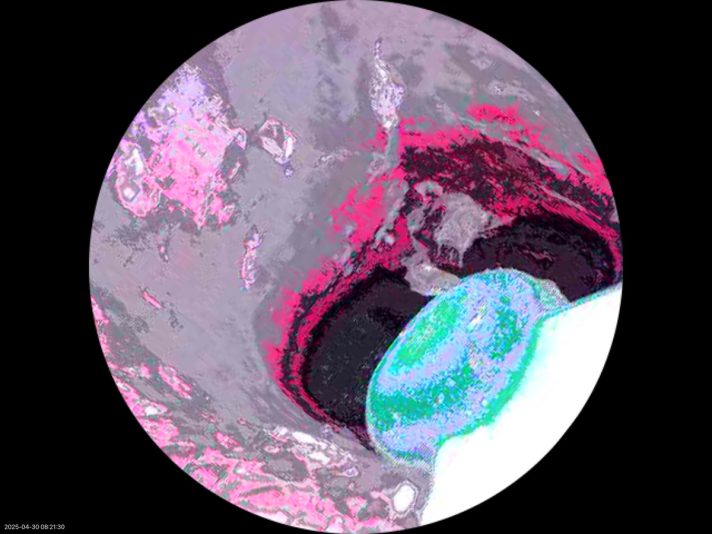

・プレデターの視界

プレデターが見たヤスミノの耳の中